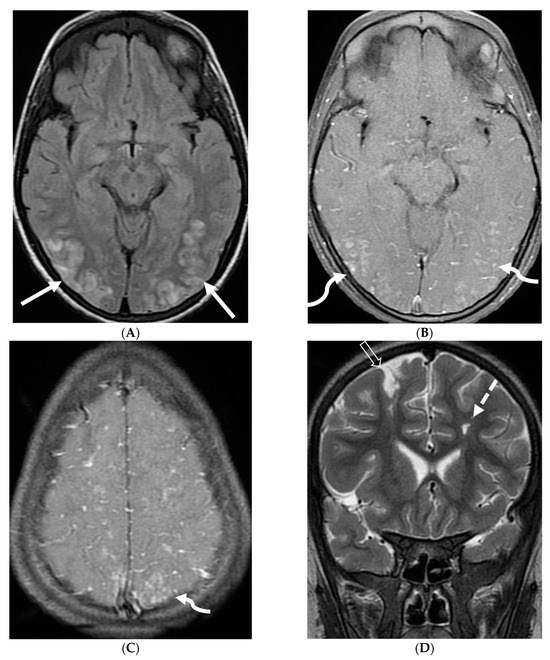

5.3. Anti-Myelin Oligodendrocyte Glycoprotein (MOG) Demyelination

Anti-MOG antibody associated demyelination (MOGAD) frequently presents as Acute Disseminated Encephalomyelitis (ADEM) in children and opticospinal involvement in young adults [105]. Bilateral but asymmetric T2 hyperintense lesions occur in thalamus, pons and cerebellar peduncles are common in children [106]. Optic nerve involvement typically presents as a long segment with anterior predominance, in contrast to the posterior predominance seen in Neuromyelitis Optica Spectrum Disorders (NMOSD) and the short segment involvement characteristic of Multiple Sclerosis (MS) [106].

LME has been shown to present early in the disease course and is much more common in children (33%) compared to adults (8%) [107]. Gadde et al. found that 8% of pediatric MOG antibody-associated demyelination cases had only LME without any other central nervous system manifestation. LME when present can be particularly helpful in differentiating from NMOSD [106]. Furthermore, Valencia-Sanchez et al. reported a significant association between LME and cerebral cortical encephalitis in MOG antibody-associated disease. This finding suggests that LME may be an important marker for cortical involvement and potentially more severe disease (Figure 21) [108].

Figure 21.

Sagittal T2 (A,B), axial FLAIR (C), axial T2 cervical spine (D) at the level of C7 vertebral body and Axial T2 orbits (E): 12-year-old girl presented with right focal motor seizure and left temporal lobe slowing on electroencephalogram (EEG). Right eye vision loss and irritability. Ill-defined areas of signal abnormalities are identified within the RIGHT mesial temporal lobe and bilateral medulla (white arrows). FLAIR hyperintensity is identified on the left central sulcus (black arrow). Small focus of signal abnormality is seen on the right side of the cord at the 7th cervical vertebra (C7) (dashed arrow). There is also bilateral papilledema (arrowheads). Post contrast axial T1 (F,G), axial T1 orbits (H) and axial T1 cervical spine at C7 (I): Asymmetric LME (black arrows) predominantly involving the left cerebral hemisphere, with minimal right parietal involvement is seen. Ill-defined enhancement in the right mesial temporal lobe, and right greater than left medulla (white arrows) corresponds to the signal abnormality. There is right greater than left, optic nerve enhancement (curved arrow). Single small enhancing lesion in the spinal cord on the right at the level of C7 corresponds to the signal abnormality (dashed arrow). Features favor a demyelinating process. MOG antibodies were positive at 1:20 in keeping with Myelin oligodendrocyte glycoprotein (MOG) antibody disease (MOGAD).